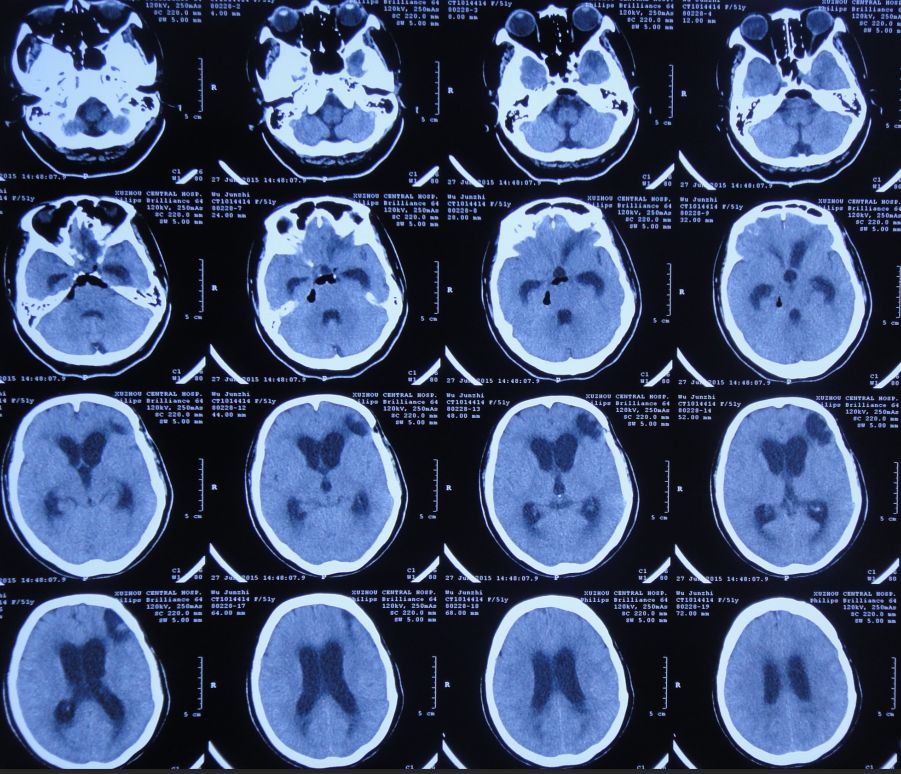

2015年7月27日患者突发高热,体温高达39.0 ℃,伴呕吐,意识转差,腰椎穿刺颅内压力极高,并留取脑脊液进行细菌培养;复查头CT检查显示脑室系统显著扩张,颅内积气(图11)。当日急诊进行了右侧侧脑室钻孔引流术,术后入住ICU给予重症监护、抗炎、抑酸等治疗。

图11:2015年7月27日头CT:脑室系统显著扩张,颅内积气